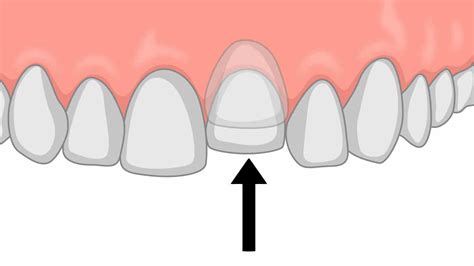

La intrusión dental se define como un movimiento del diente causado por factores fisiológicos, mecánicos o movimientos de ortodoncia. Se caracteriza por el desplazamiento vertical del diente hacia el interior de la cavidad bucal.

En los casos más severos (Grado III), la corona dental no es visible clínicamente, lo cual representa un reto para el odontólogo, especialmente en niños y adolescentes.

- Exámenes físicos intrabucales: Evaluación de la posición del diente y su desplazamiento en la cavidad bucal. Se puede notar con exactitud si la corona del diente se encuentra desplazada en la cavidad bucal.